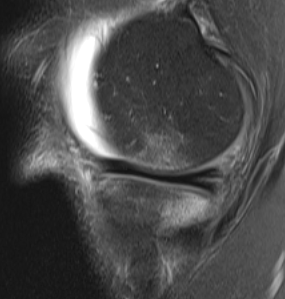

Normal ACL on MRI

Characteristics

- straight structure

- able to see continuity of fibres from tibial to femur

- parallel to intercondylar notch

- no anterior subluxation of the tibia

- normal to have some increased signal due to adipose and synovial tissue